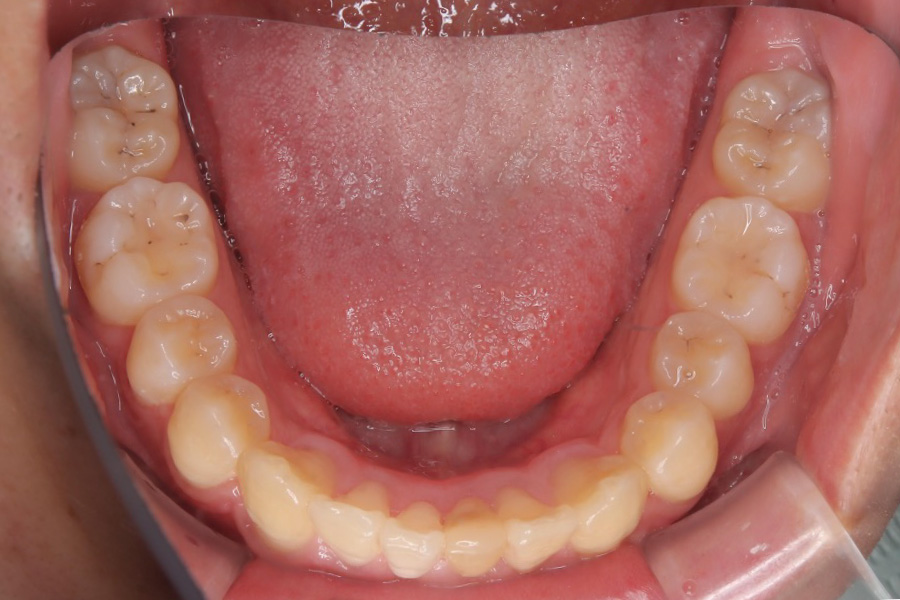

治療前

主訴 突出感、ガタつきが気になる